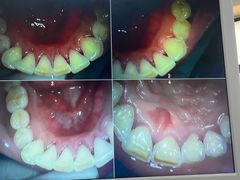

• -牙博士口腔品牌连锁(杨浦店)

fairy7_7 | 22-07-28

报错